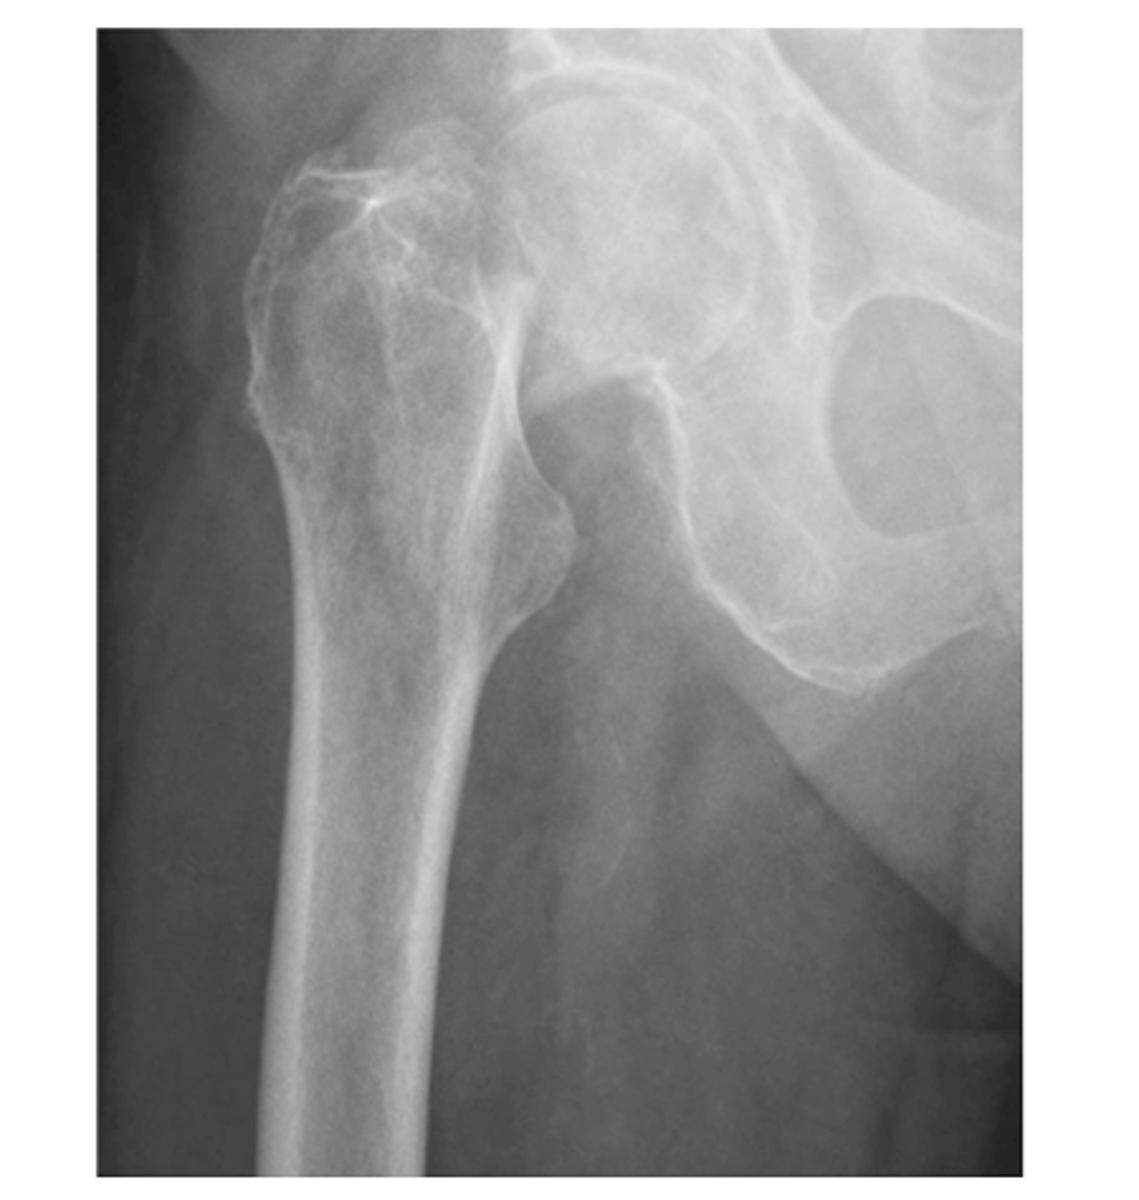

A: alignment...femoral neck fracture (the greater trochanter is superimposing on the head)

Describe the MOST obvious "ABCS" component.